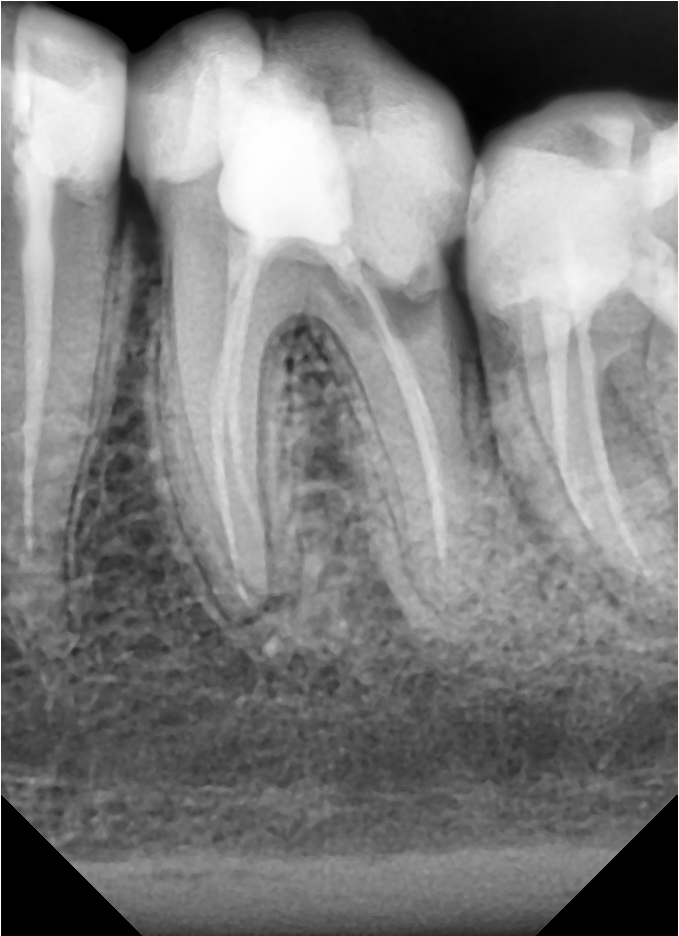

По истечении нескольких месяцев врач делает рентгеновский снимок. Если периодонтит вылечен, убирает временную пломбу, заполняя корневой канал постоянным материалом, восстанавливая первоначальный внешний вид коронковой части.

Лечение хронического периодонтита представляется трудоемкой процедурой, ввиду чего настоятельно не рекомендуется запускать болезнь до этой стадии. Комплекс задач, стоящих перед специалистом, похож на реализуемый при лечении острой формы. Отличается лечение лишь используемыми материалами и продолжительностью каждого из этапов. Если фиброзный отличается только отсутствием необходимости расширения корневого отверстия, то гранулирующая и гранулематозная форма подразумевают установку временной пломбы на срок до одного года.

В течение этого временного интервала пациент проходит курс терапии, регулярно посещая кабинет специалиста для рентгеновского обследования, позволяющего контролировать состояние зуба.

Кто работает с микроскопом, тот видел сколько бывает устьев в полости зуба и дополнительных разветвлений в корневом канале. И подчас, мы врачи не всегда можем их качественно обработать и обтурировать (пломбировать). Оставляем мумифицирующие жидкости, промываем сильными антисептиками с ультразвуком, проводим временное пломбирование. Делаем со своей стороны всё, чтобы не оставалось инфекции в корневом канале. И процент успешного лечения все-таки больше, чем неудач.

- Делать снимок с инструментом, не выводя его за верхушку корня и только потом на выверенной длине начинать очищать корневой канал.

- Делать контрольные снимки и окончательный результат.